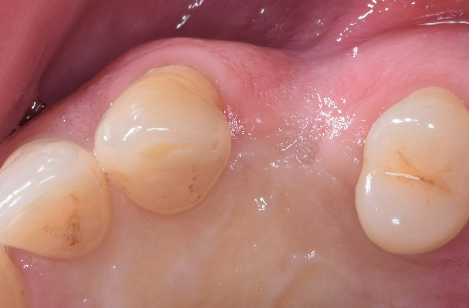

După perioada de osteointegrare a implantului acesta se descoperă, adică se creează o cale de comunicare cu mediul bucal, el până în această etapă fiind acoperit de gingie. Se instalează apoi un bont de vindecare care are rolul să ghideze vindecarea gingiei în jurul implantului.(Fig. 3.5.5 și 3.5.6) Cu acest bont pacientul așteaptă o perioadă variabilă de 14-21 de zile, iar dacă după acest interval gingia este vindecată, se poate trece la etapa următoare – cea de amprentare.